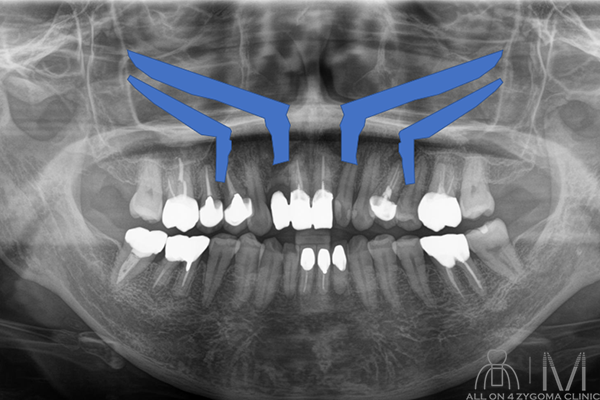

歯槽骨の頬舌方向のボリュームが少なくノーマルインプラントの埋入が困難である事が示唆された。前歯部と臼歯部で歯槽堤の高低差が大きいことから、安定度を高めるプラットフォームの設計が必要であると考えた。また、頬骨に十分な厚みがある事からザイゴマインプラント4本を用いるオールオン4ザイゴマインプラント治療 (EZ4) を計画した。手術を円滑なものとする為、術中は静脈内鎮静法下での手術を予定した。